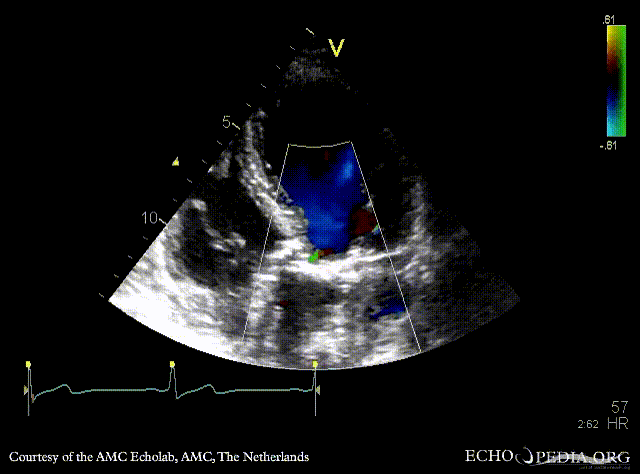

PLAX: stenotic aortic valve, left ventricle hypertrophy PLAX with Color Doppler: mild aortic regurgitation